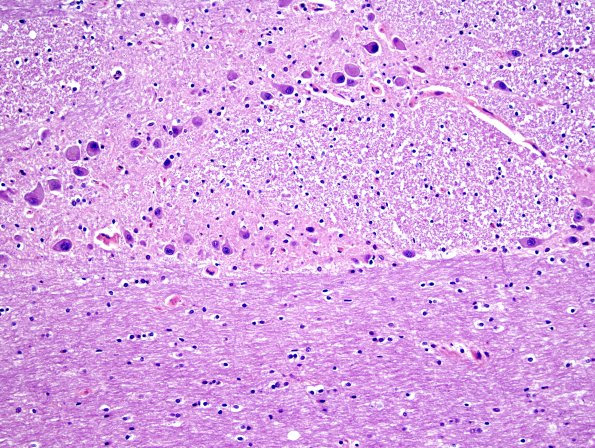

The basis pontis in a normal adult demonstrating pontine nuclei, transverse and descending tracts at several descending tracts. (H&E)